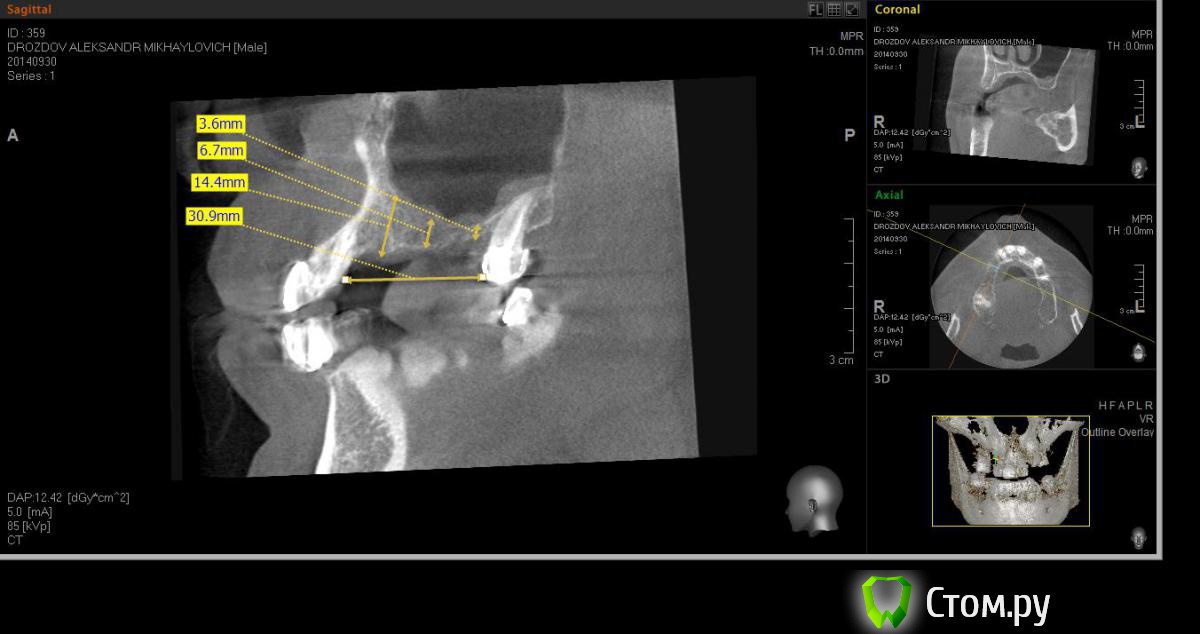

Neilrus Опубликовано 5 октября, 2014 Поделиться Опубликовано 5 октября, 2014 (изменено) Здравствуйте. Помогите добрым советом отностительно имплантата 26з , высота примерно 7,5 до пазухи, ширина впечатляет, почти 9,5.Планируем имплантацию вч. С первым квадрантом все ясно, синус на два дистальных имплантата с латеральным доступом. Ставим систему Xive. Второй квадрант, хочу попробовать систему AnyRidge, они есть очень широкие за счет лопастей резьбы с узким телом, площадь обещают на 50 % больше чем у аналога такой же высоты и диаметра, не хочется ему второй синус без необходимости делать. ВОПРОС: Поставить во второй квадрант Xive широченный и короткий с поднятием крыши пахухи крестально на 0,5-1 мм 5,5*8 чтобы с обеих сторон была одинаковая система?Либо поставить AnyRidge высотой 6,5*7 без вмешательства в пазуху ? но тогда разная система с двух сторон, ни разу так не протезировал, это будет проблемой? Как вы считаете? Прикалываю фото кт 26 зуба, и заодно первый квадрант для интереса.Спасибо. Изменено 5 октября, 2014 пользователем Neilrus Ссылка на комментарий